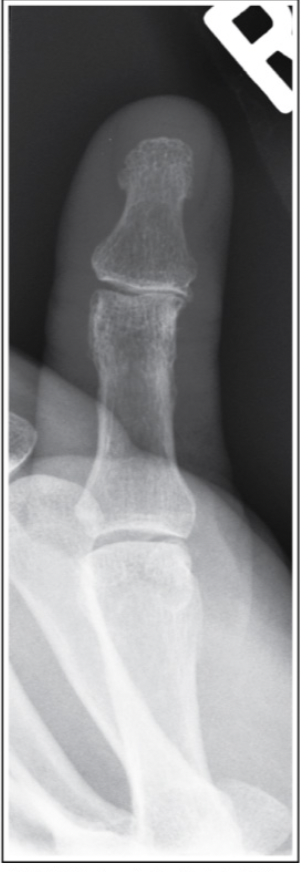

What image criterion is not met on this AP projection of the thumb?

a.Interphalangeal joint space in profile

b.Proximal and distal phalanges demonstrated

c.First metacarpal-phalangeal joint is free of superimposition

d.First metacarpal-carpal joint is shown free of superimposition

A